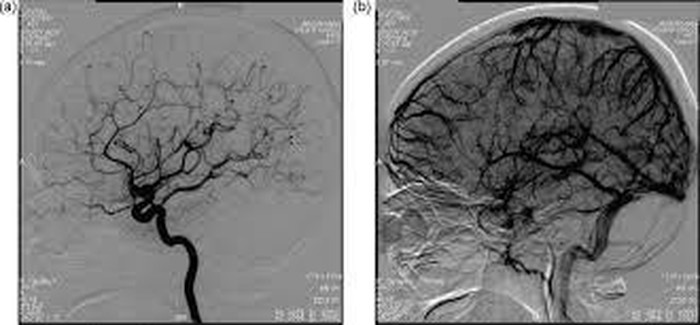

Kasus ini pun ditangani oleh Spesialis Neurologi Konsultan Neurointervensi di Mayapada Hospital Bandung dr Condrad MP Pasaribu, SpN (K), FINS. Ia melakukan tindakan Angiografi Otak atau Digital Substraction Angiography (DSA) pada pasien untuk melihat dan mendeteksi masalah pada pembuluh darah yang ada di dalam atau yang menuju otak.

Dari hasil DSA, diketahui bahwa keluhan pasien disebabkan oleh trombosis vena cerebral, yakni adanya penyumbatan pada pembuluh darah vena di otak. Menurut penuturan dr Condrad, DSA adalah prosedur diagnostik untuk melihat gambaran pembuluh darah otak dan juga leher.

Dengan tindakan DSA ini kita bisa melihat masalah apa yang terjadi di dalam pembuluh darah otak. Apakah ada penyempitan di pembuluh darah arteri atau vena, penggelembungan pembuluh darah (aneurisma), malformasi pembuluh darah, dapat juga melihat lokasi dan derajat penyumbatan, berguna pula untuk mengevaluasi aliran pembuluh darah, dan membantu dokter untuk memetakan terapi yang sesuai dengan kelainan yang dialami pasien.

Foto: Mayapada Hospital |